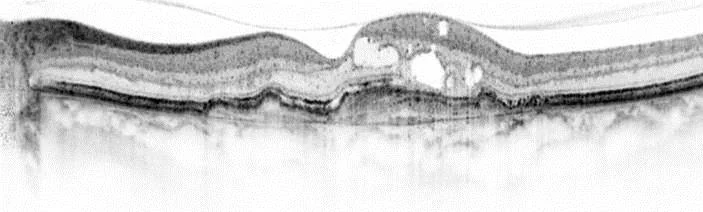

Optische Kohärenztomographie Zurück